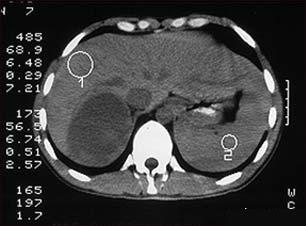

Sindromul Cushing - hipercorticismul